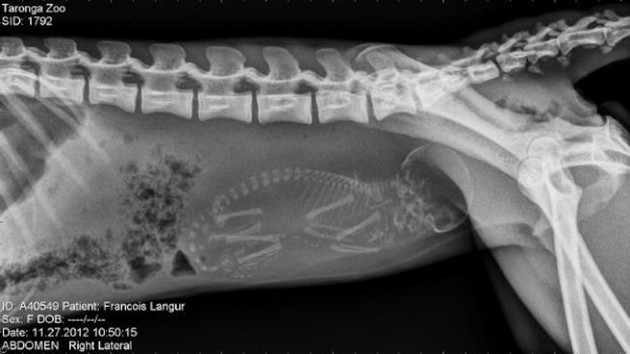

Radostné očakávanie môže u rôznych zvieracích druhov vyzerať všelijako. Fotky, ktoré vám dnes ukážeme sú raritné a rozhodne zaujímavé. Predsa len, videli ste už niekedy tehotné zvieratá cez röntgenové snímky?

Niektoré z nich rodia živé mláďatá, iné zasa kladú vajíčka. Zrod nového života vo zvieracej ríši je každopádne fascinujúci. A ako vyzerajú tehotné zvieratká sa môžete pozrieť na nasledujúcich “lekárskych” snímkoch.

Opička langur